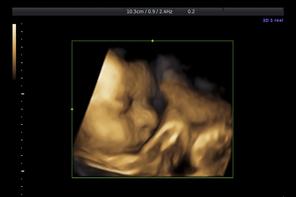

Trudovi označuju početak porođaja i mogu se promatrati kao svojevrsni znak upozorenja. No, zapravo, trudovi su prisutni…